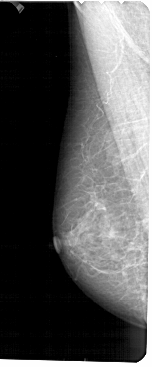

A_1489_1.LEFT_MLO

A_1489_1.RIGHT_MLO

LEFT_MLO LINES 5491 PIXELS_PER_LINE 2266 BITS_PER_PIXEL 12 RESOLUTION 43.5 NON_OVERLAY

RIGHT_MLO LINES 5491 PIXELS_PER_LINE 2116 BITS_PER_PIXEL 12 RESOLUTION 43.5 OVERLAY

LESION_TYPE CALCIFICATION TYPE PLEOMORPHIC DISTRIBUTION CLUSTERED

ASSESSMENT 4

SUBTLETY 2

PATHOLOGY MALIGNANT